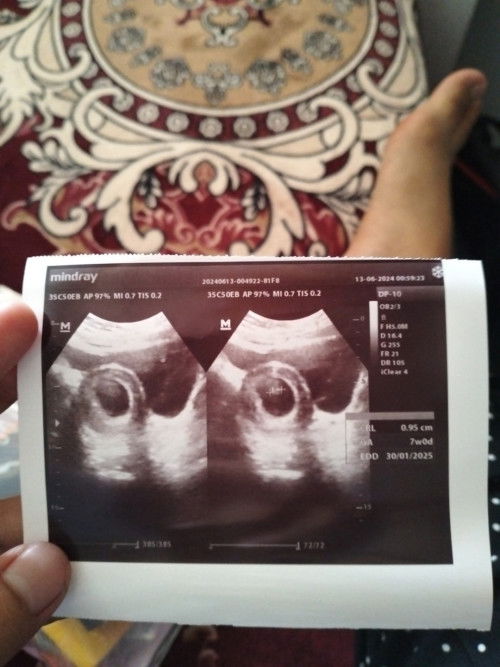

Usia kehamilan 7week Baru kelihatan janin nya Belum ada djj nya normal ngga ya Bun??

Apakah normal ya Bun?? Ukurannya janin nya baru 0, 95 normal ngga Bun? Agak ovt soalnya pernah ada riwayat keguguran 8 week